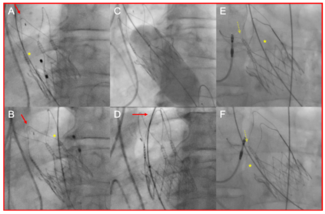

A 25-year-old female patient with a 30-mm ostium secundum atrial septal defect received a transesophageal echocardiogram-guided device closure. The 32-mm Amplatzer atrial septal occluder (ASO) device was carefully prepared and loaded through...